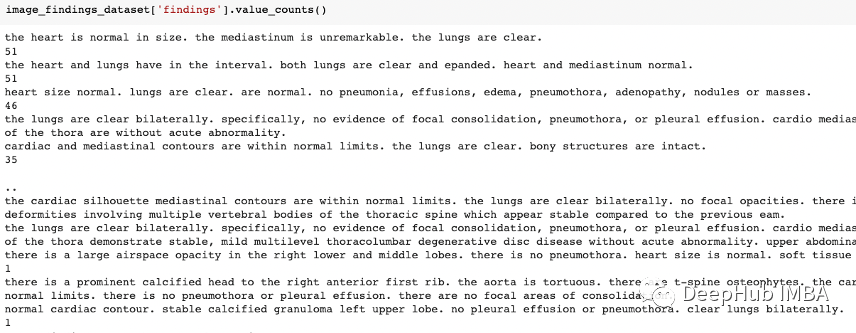

使用XML库,我们从每个患者XML报告中提取“发现”、图像路径和患者id信息,并与它们形成一个数据集。

针对于“发现列”的数据处理

在发现列中大约有13%的空值。我们将删除在结果列中具有空值的行,因为没法用随机的结果填充空值。并将其转换为小写,删除垃圾词

理解统计结果

我们可以看到像胸腔积液(pleural effusion),气胸(pneumothora),心脏纵隔轮廓( cardiomediastnal silhouette),yi一般情况下我们认为这些词不是正常词,但这些是医学领域特有的,并且出现的频率很大,说明预处理后看起来很干净。